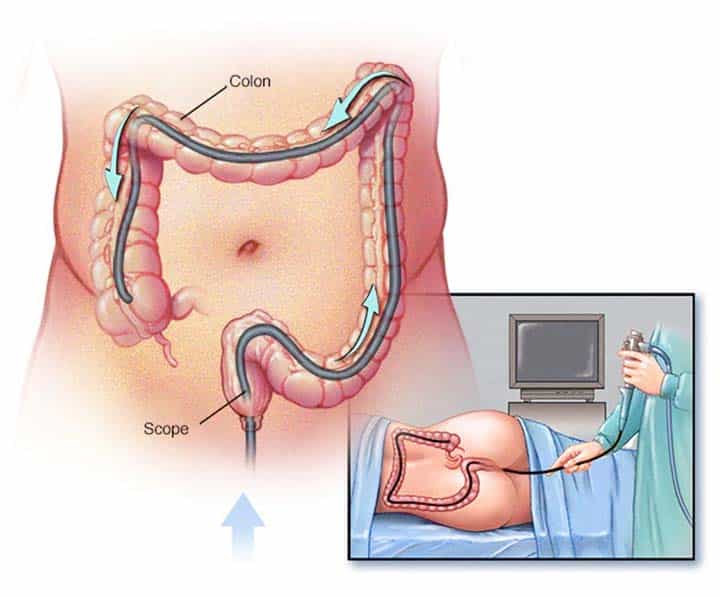

در این روش، لولهای باریک و انعطافپذیر به نام کولونوسکوپ، با ضخامت تقریبی یک خودکار، از طریق مقعد وارد روده بزرگ میشود. این روش تشخیصی معمولاً برای افرادی تجویز میشود که دچار تغییر در الگوی اجابت مزاج، خونریزی مقعدی، آزمایش خون مثبت در مدفوع یا سابقه خانوادگی سرطان روده بزرگ هستند.

به زبان ساده، کولونوسکوپی نوعی آندوسکوپی است که در آن یک آندوسکوپ مجهز به دوربین به پزشک اجازه میدهد بخشهای مختلف روده بزرگ را مشاهده کند. این ابزار انعطافپذیر علاوه بر دوربین، دارای اسکوپهای کوچکی است که پزشک با کمک آن میتواند بافتهای غیرطبیعی را از روده بزرگ بردارد. همچنین در طول Colonoscopy امکان نمونهبرداری از بافتها (بیوپسی) نیز وجود دارد. حال که با مفهوم کولونوسکوپی آشنا شدید، وقت آن است که درباره دلایل انجام آن و نحوه اجرا شدن این روش اطلاعات بیشتری کسب کنید.

نحوه انجام Colonoscopy به شرح زیر است:

- زمانی که برای Colonoscopy آماده شدید، پزشک از شما میخواهد به صورت راحت و در حالت جنینی روی تخت دراز بکشید.

- کولونوسکوپ از طریق مقعد وارد روده بزرگ میشود. در گذشته ممکن بود کمی درد احساس کنید، اما امروزه اغلب کولونوسکوپی با بیهوشی یا آرامبخش انجام میشود و شما در طول عمل دردی حس نمیکنید.

- گاز دیاکسیدکربن به داخل روده بزرگ وارد میشود تا روده کمی منبسط شود و پزشک بتواند جزئیات داخلی آن را بهتر مشاهده کند.

- کولونوسکوپ به آرامی از طریق روده بزرگ پیش میرود تا در صورت نیاز به روده کوچک برسد.

- در طول حرکت دستگاه، کاتتر هوا روده را باد میکند و دوربین تصاویر و فیلمهای زنده از داخل روده برای نمایش روی مانیتور ضبط میکند.

- پزشک تصاویر را با دقت بررسی میکند تا نواحی و بافتهای غیرطبیعی شناسایی شوند.

- پس از رسیدن کولونوسکوپ به انتهای روده بزرگ، دستگاه به آرامی خارج میشود و در حین خروج نیز دیوارهها و بافتها مجدداً بررسی میشوند.

نحوه ورود لوله و تصویربرداری داخلی

کولونوسکوپ از طریق مقعد وارد میشود و این لوله انعطافپذیر با هدایت دقیق پزشک متخصص بهآرامی در داخل روده بزرگ حرکت میکند. تصویربرداری و نحوه حرکت کولونوسکوپ داخل روده بزرگ را میتوانید در تصویر زیر مشاهده کنید.